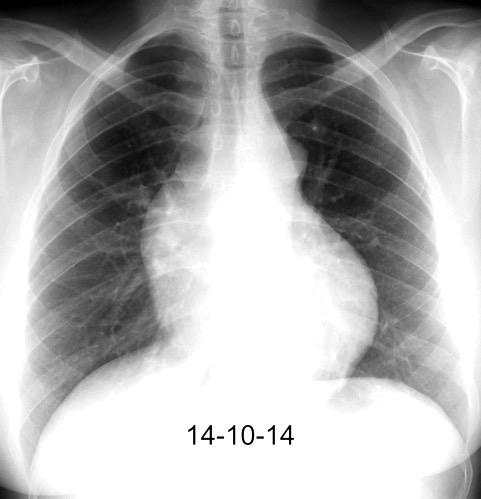

Síntomas y signos que se producen con la obstrucción total o parcial de la vena cava superior

Causas Malignas +/- 90-95%

Ca. Broncogénico (80-85%)

Linfoma No Hodgkin (15%)

Catéteres, shunts y marcapasos…23%

T. Mediastínico. Bocio

Fibrosis Idiopática

Tb, Histoplasmosis, Actinomicosis, Sarcoidosis

Carcinoma microcítico con síndrome de VCS

Grupos:

1. Obstrucción por encima de la V Ácigos. (La sangre llega al corazón a través de ella)

2. Obstrucción con participación de la V. Ácigos. (La sangre utiliza otras alternativas para llegar al corazón vía VCI).

Participación de la V. Ácigos como vía principal para llegar a la VCI.

Visible: 88%